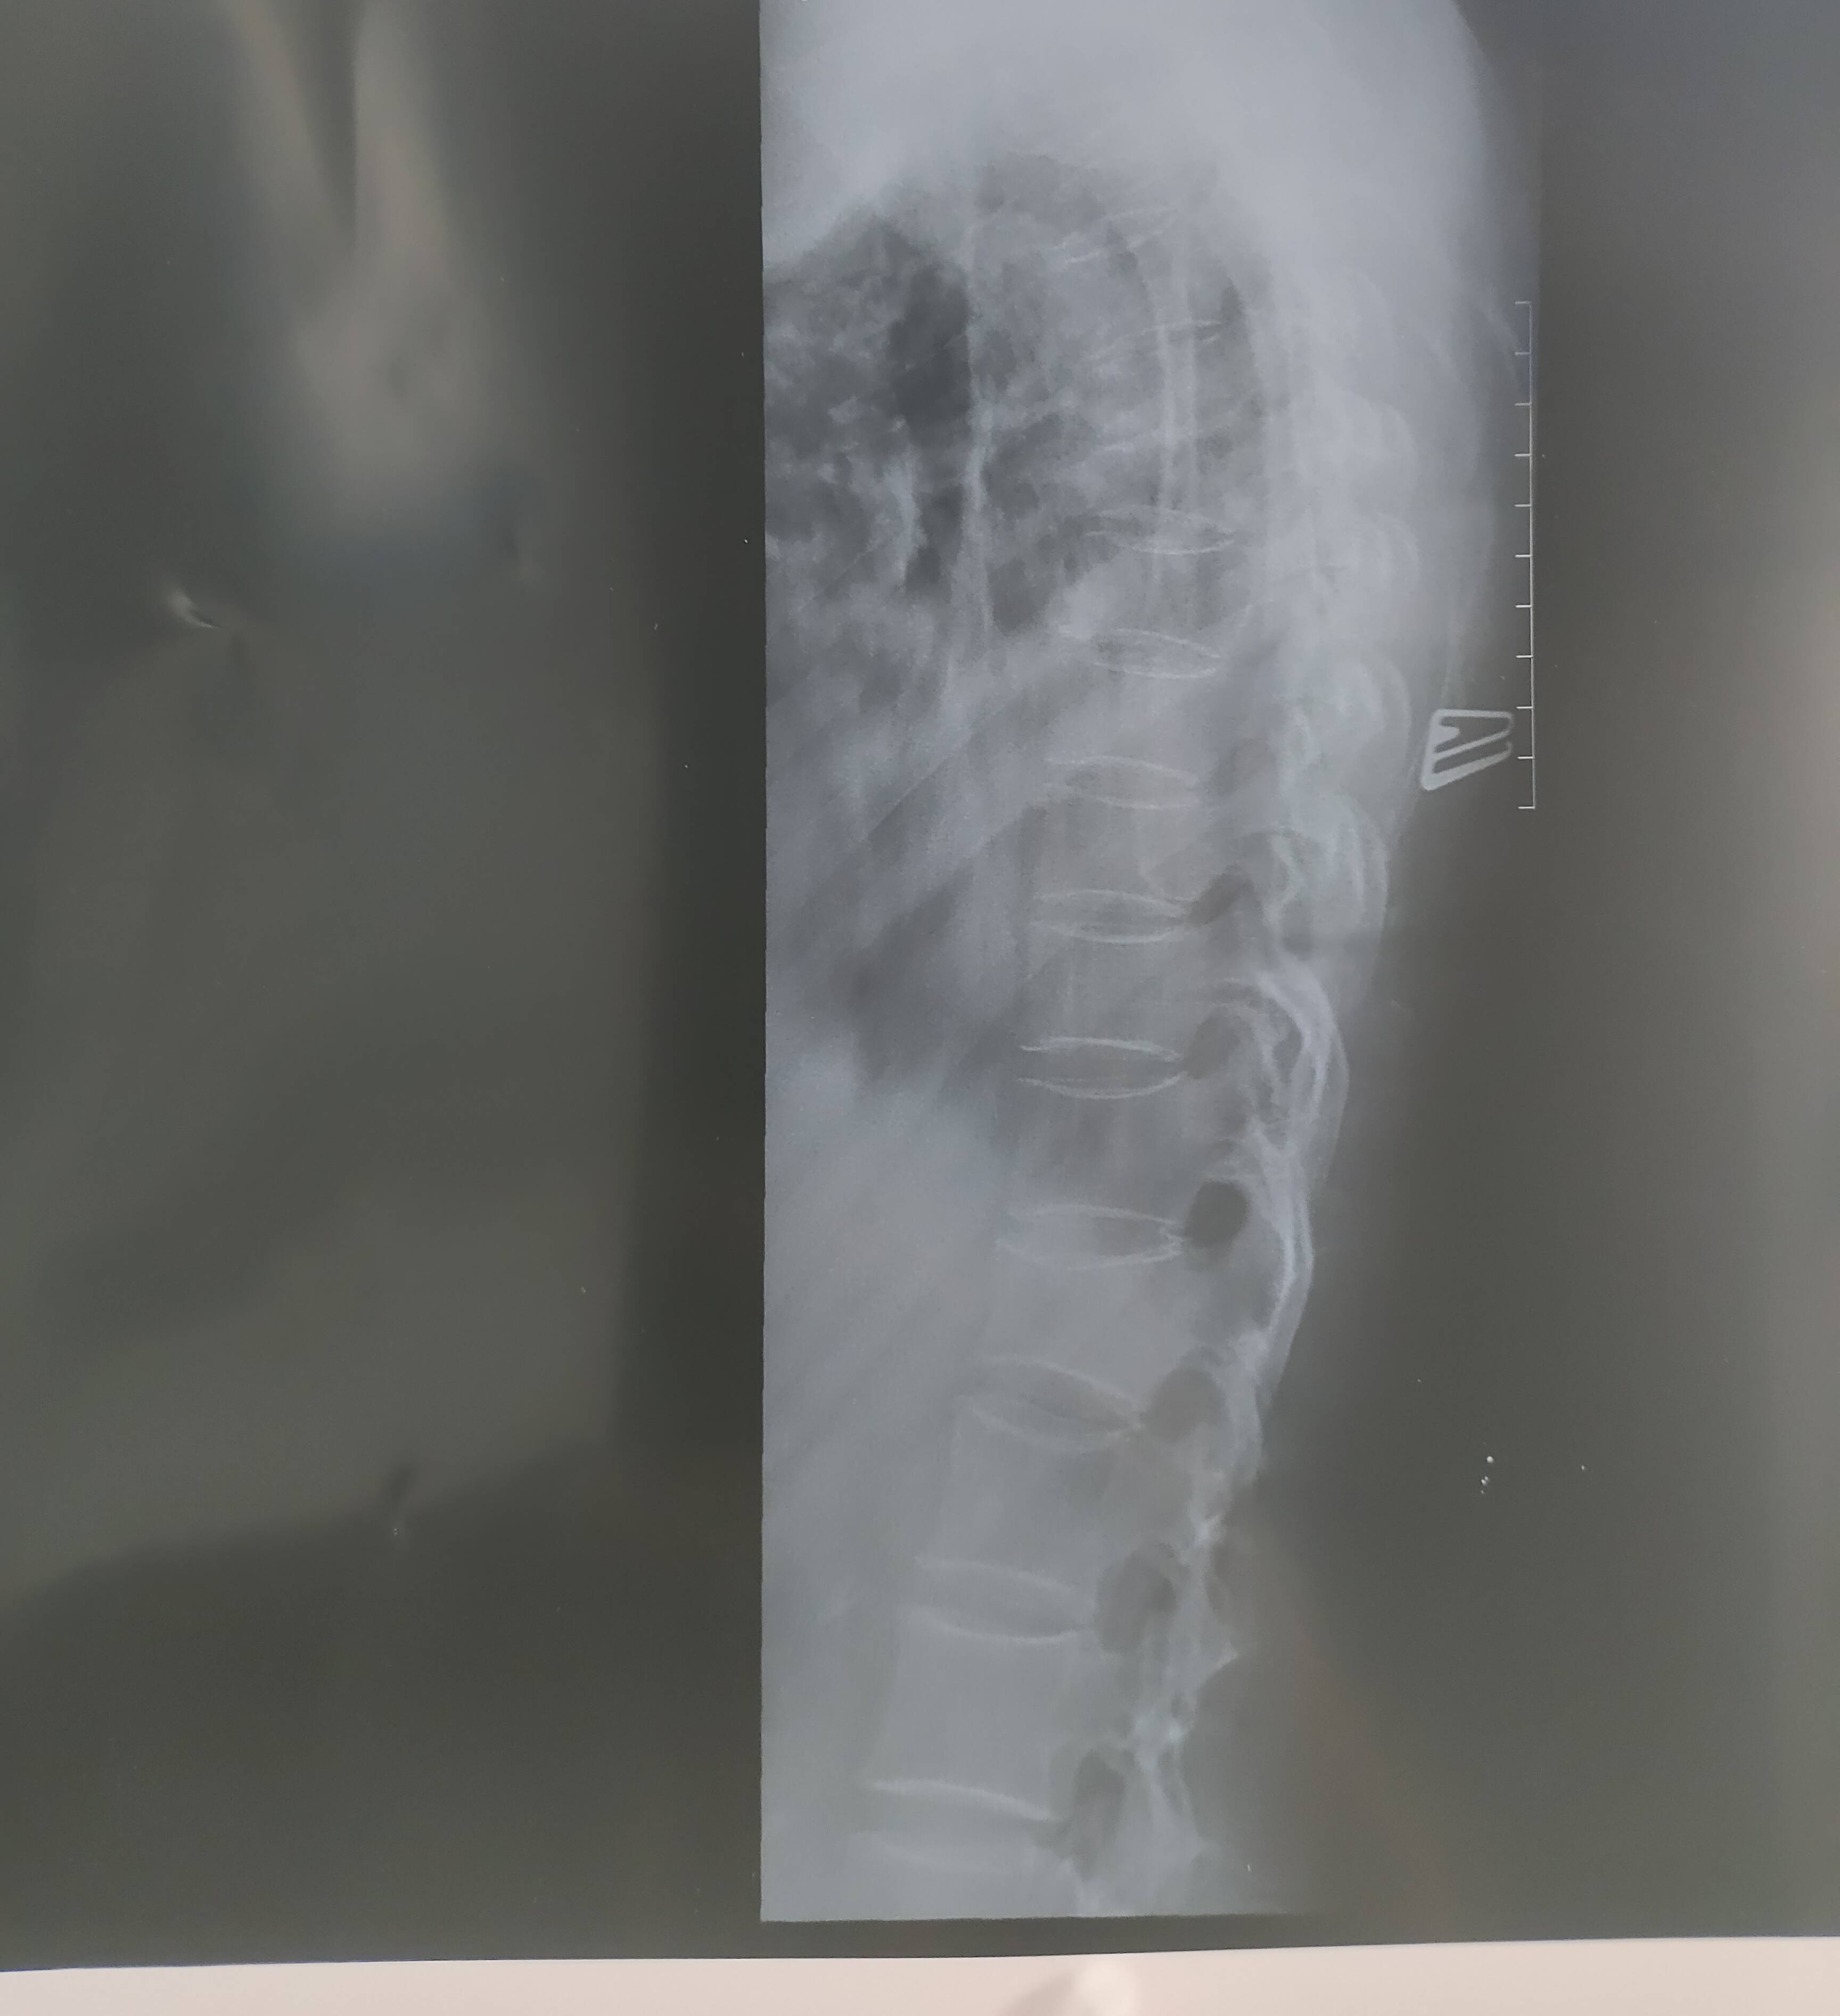

奥希吃几天,临时急拍了头核磁,医生说考虑脑转,让只吃奥希复查即可,请大家看看,这脑转用单独看看吗,严重吗,什么趋势? 另外骨转已打地舒一针,这个片子报告提示胸椎变形,考虑骨转移,还没全身骨扫描,这片子可参考90%吗,继续打地舒,还是完善全身骨扫描,用作pet吗?身体妇科 b 超 乳腺 肾 腹部,都有拍片。桥本甲状腺,弥漫性肾。